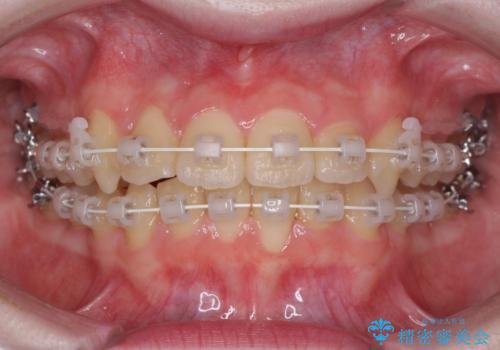

- 矯正装置

- 審美装置

インビザラインでの自己管理は難しいとのことで、ワイヤー装置にて矯正を行うこととしました。

治療途中で大学受験があり、来院できない時期がありましたが、2年以内で満足のいく歯並びを達成することができました。